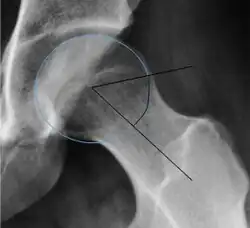

Projectional radiography ("X-ray") is often considered first line for FAI.[10] Anterior-posterior pelvis and a lateral image of the hip in question should be attained.[10] A 45-degree Dunn view is also recommended.[10][19]

| Alpha angle | ![]() |

Degree of bulging of the femoral head-neck junction: In normal conditions there is a symmetric concave contour at the junction of the femoral head and neck. Loss of this concavity or bone bulging may lead to cam type impingement. The degree of this deformity can be measured by the alpha angle. Although it can be measured in the cross-lateral view, the 45° Dunn view is considered more sensitive and the frog leg view more specific in determining pathologic values. |

|